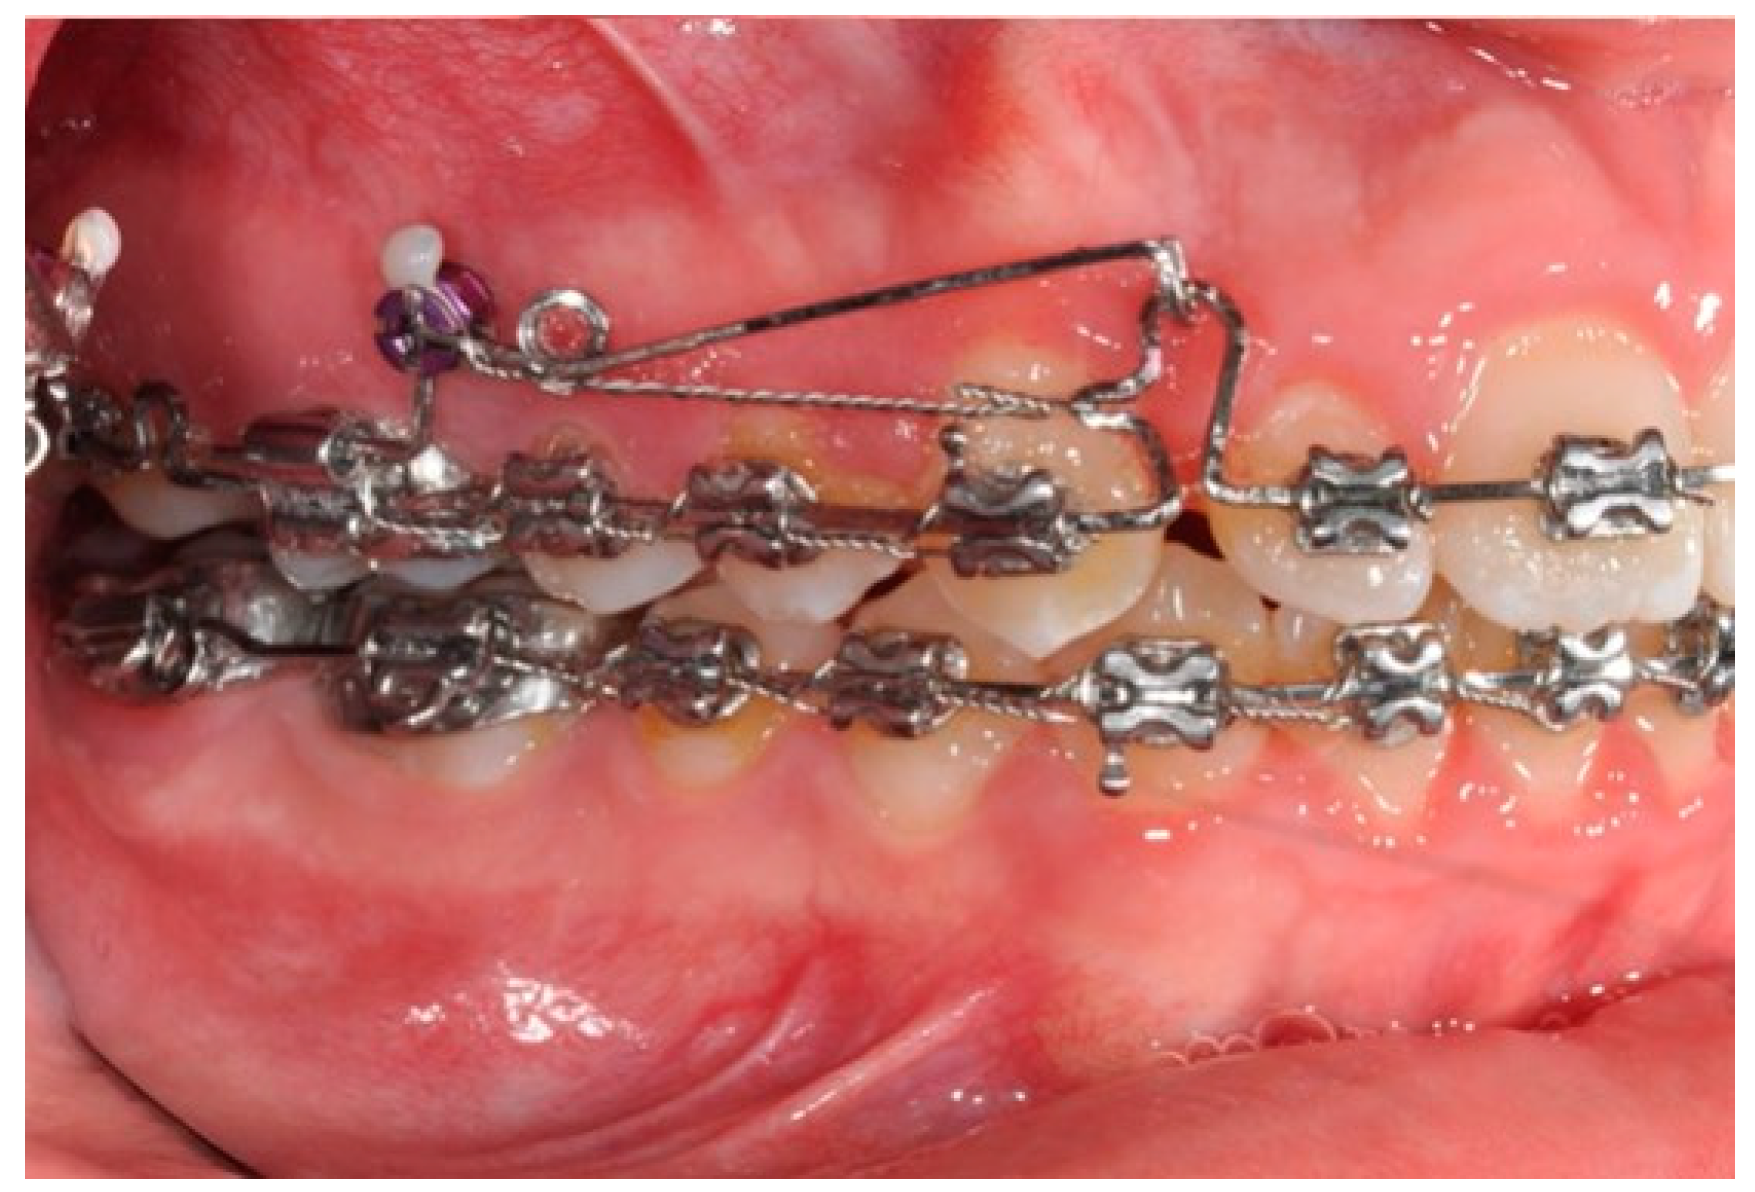

A 12-year-old girl with the second skeletal class (ANB 5), a high angle (FMA 27), and a facial index of 0.67 was selected. Soft tissue analysis showed a convex profile with a Z angle equal to 57 and an FMIA angle close to 55. The IMPA angle was 98. The analysis of the dental cast revealed a spee curve of 3.5 mm (Table 1). The occlusion presented a first molar class to the left, and a light second class to the right with 1 mm crowding in the lower jaw. The overjet was 0. The upper canines were impacted (Figure 1, Figure 2 and Figure 3). The patient’s chief complaint was altered aesthetic perception due to reduced dimensions of the deciduous canines. The treatment objectives were to retrieve space for upper canines’ eruption, level the spee curve, upright the lower incisors, and reduce the impact of the convex profile through occlusal vertical control to facilitate counterclockwise mandibular rotation.

Figure 1. Initial intraoral photos.